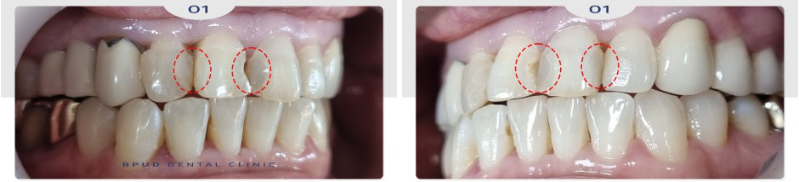

오늘은 전치부 충치로 인해

부평치과 앞니치료를 진행하신

환자분을 소개해 드리도록 하겠습니다.

환자분께서는 앞니가 썩어서

보기가 좋지 않으시다며 치료를 위해

내원해 주셨는데요.

오래전, 이미 충치로 인해

사이사이 때워 놓은 재료들이 떨어지고

2차 우식도 진행이 되었음을

관찰할 수 있었습니다.